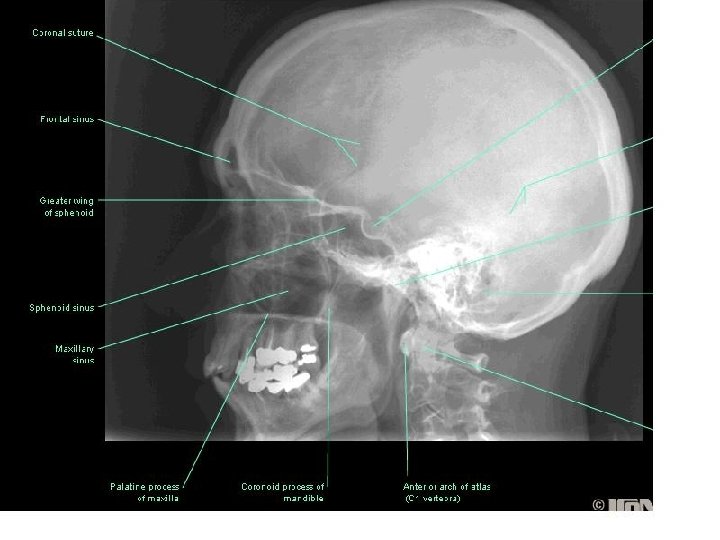

Nasal cavity Nostriles (nares) Choana Roof: body of the sphenoid, cribriform plate of the

Nasal cavity Nostriles (nares) Choana Roof: body of the sphenoid, cribriform plate of the ethmoid, frontal bone, nasal bones, nasal cartilages Floor: maxilla, palatine Medial wall: nasal septum Lateral walls: contain sup. , middle & inf. Nasal conchae.

Paranasal Sinuses

Sphenoid sinus